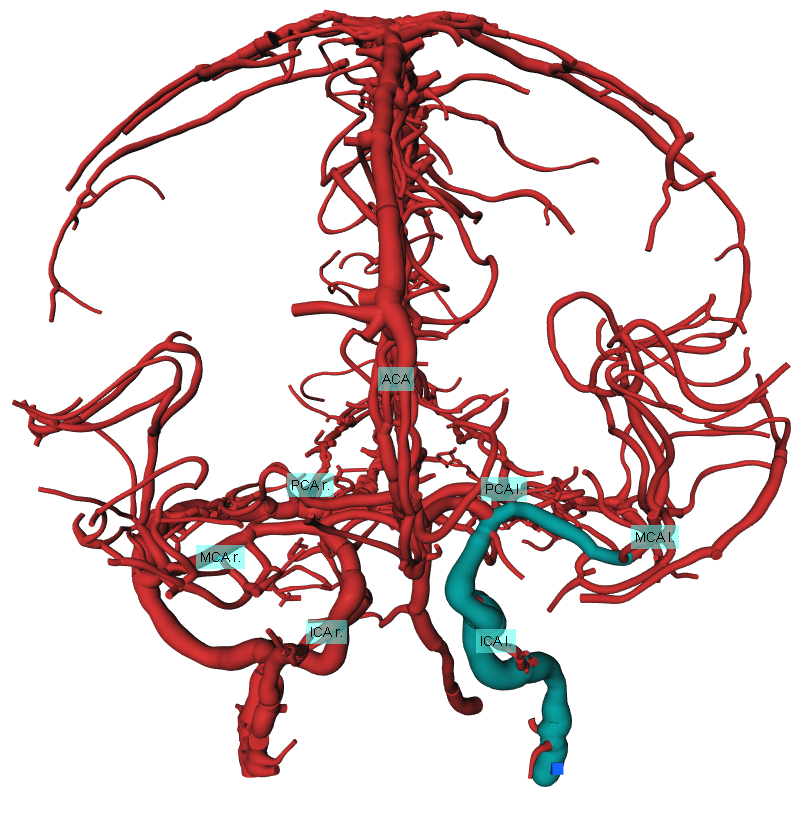

For the interactive part of our work, the segmentation must be modeles as geometric representation e.g. as graph of centerlines and lumen radii. First, as tiny gaps may occur in the segmentation, closing is applied, followed by the Distance-Transform-Skeletonization algorithm (short, DTF-Skeletonization) (Selle, 2000), which returns not only the skeleton itself but also a surface model of the vascular structures. Examples trees are shown in Fig. 3, Fig. 5, Fig. 5 and Fig. 6(a). Once the model is available, the information required of the interactive masking (geodesic distances) is computed in Fig. 2(k). As the processing consists primarily of searching pathways on the skeleton representation, the step is called “Graph Search”. In Sec. 4.2.1 we present the generic concept of pathway searches on vessel trees, from which it is possible to derive applications. Exemplarily, we present two applications consequently following from the formal concept introduction, namely the interactive path search in Sec. 4.2.3 and the interactive suppression of veins in Sec. 4.2.2.

In some cases, for instance if large contrast boluses were injected, veins like the sinus sagittalis may disturb the visual impression. The second search node property enables an easy way of displaying only relevant parts by placing the root node into the Circle of Willis and visualizing only nodes and their paths accessible within a certain geodesic distance. Fig. 3 shows two trees on different geodesic distances. The lower tree is from a patient who suffers an LVO on the left MCA branch, while the top one is LVO negative, showing no noticeable defects. As displayed, veins and more distant vessels may conceal stroke-relevant parts in their full representation on the right end and disappear towards the left side while the distance is decreased.

To determine the presence or absence of a vessel, we propose the following approach. Each marker is assigned a fixed per-vessel maximum allowed distance. For each marker, the shortest distance to the vessel mask is computed. If the mask is within each marker’s maximum allowed distance range for a certain number of markers per vessel, that vessel is identified as present. If not enough markers are close enough to the mask, the vessel is considered as missing or occluded. The positions, distances, and the number of markers per vessels are available upon request. To place the final labeling marker for visualization purposes, either the marker with the shortest distance can be selected or the voxel on the segmentation mask with the closest distance to the marker set. Final labeling markers are shown in Fig. 5 for MCA l. and r., PCA l. and r., ICA l. and r. and ACA viewed sagital posterior on the vessel tree model.